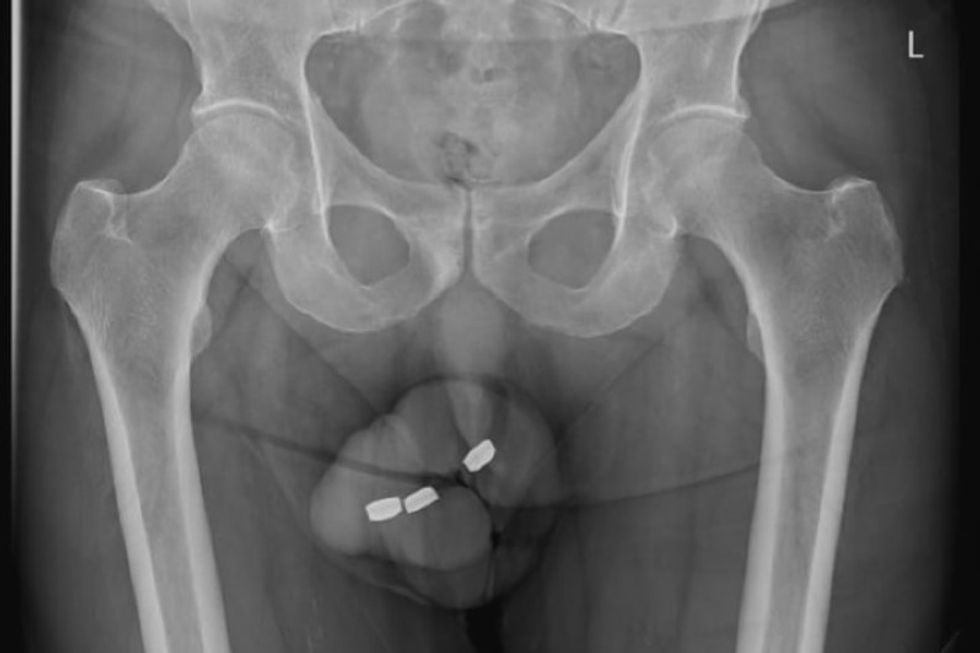

Një burrë 73-vjeçar australian u detyrua t'i nënshtrohej një operacioni në uretrën pasi i kishte ngecur brenda penisit një bateri në formën e butonit.

Mjekët provuan disa metoda për të hequr bateritë, shumë prej të cilave ishin të pasuksesshme. Duke qenë se rreziku i nekrozës fillon vetëm dy orë pas lëndimit, mjekët u detyruan të punonin shpejt. Situata u zgjidh përfundimisht me pincë.